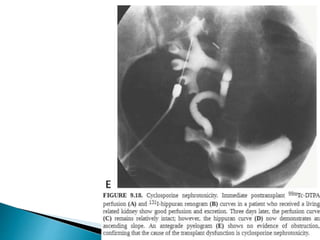

 Cyclosporine,+ prednisone,

 Nephrotoxic & hepatotoxic.

 Newer drugs, sirolimus, tacrolimus, and mycophenolate

mofetil ,permit reduction in doses of cyclosporine and

diminished nephrotoxicity at the cost of increased risk of

hyperlipidemia and diabetes.

 Cyclosporine nephrotoxicity  acute, subacute, or chronic.

 Acute toxicity potentiate and prolong the graft dysfunction

due to iscahemia.